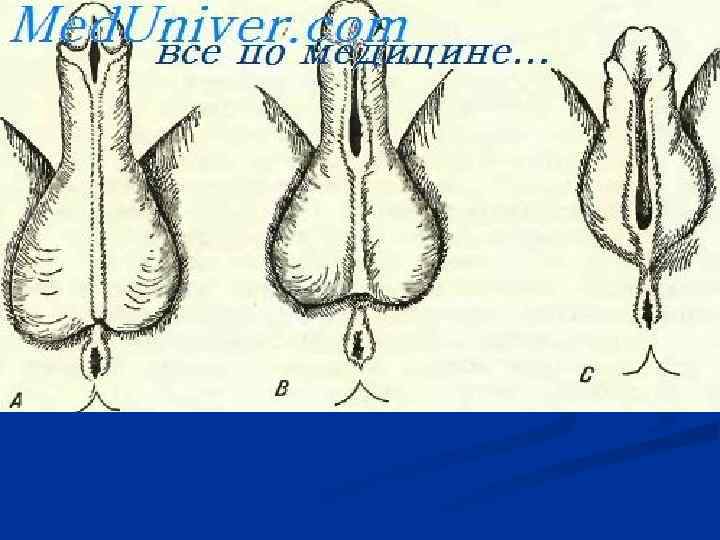

Фимоз – сужение наружного отверстия крайней плоти полового члена. Парафимоз — ущемление головки полового члена патологически сжатой кожей крайней плоти. В результате кольцеобразного ущемления головки члена крайней плотью нарушается кровоснабжение, возникает значительный отек головки. Баланит — воспаление кожи головки полового члена. Постит — воспаление внутреннего листка крайней плоти. У необрезанных мальчиков, юношей и мужчин баланит и постит всегда сопровождают друга, и в этом случае говорят о баланопостите.

Фимоз – сужение наружного отверстия крайней плоти полового члена. Парафимоз — ущемление головки полового члена патологически сжатой кожей крайней плоти. В результате кольцеобразного ущемления головки члена крайней плотью нарушается кровоснабжение, возникает значительный отек головки. Баланит — воспаление кожи головки полового члена. Постит — воспаление внутреннего листка крайней плоти. У необрезанных мальчиков, юношей и мужчин баланит и постит всегда сопровождают друга, и в этом случае говорят о баланопостите.

Иссечение крайней плоти при фимозе и парафимозе.

Иссечение крайней плоти при фимозе и парафимозе.